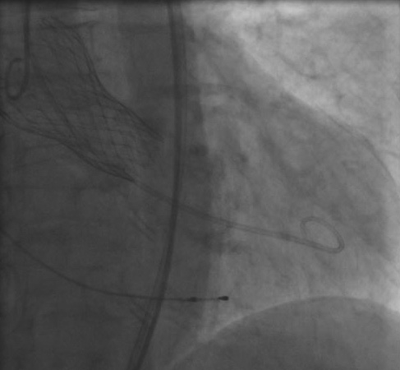

Nach gründlicher Untersuchung stand fest: Herta Grulichs Aortenklappe schleuste das Blut statt durch eine mehr als 2,5 Quadratzentimeter große Öffnung nur noch durch bedenkliche 0,6 Quadratzentimeter. Die Mediziner entschieden sich, die Herzklappe interventionell (also mit einem Herzkatheter) zu ersetzen. Die Methode ist relativ neu und wurde bislang nur an Universitätskliniken angewandt. Dabei wird ein etwa bleistiftdicker Schlauch durch ein Blutgefäß in der Leiste bis in das Herz geführt. Dort angekommen, entfaltet sich die neue Herzklappe aus biologischem Material wie eine Feder und nimmt sofort die Arbeit auf.

Die Patienten befinden sich während des gut einstündigen Eingriffs lediglich in einem Dämmerzustand und genesen in der Regel recht schnell. Auch Herta Grulich verspürte bereits nach wenigen Stunden wieder richtigen Hunger.

„Insgesamt beläuft sich der stationäre Aufenthalt auf ungefähr sieben bis zehn Tage”, erklärt Prof. Staudt. Mit der Zeit, so der Chefarzt, werde sich die jetzt auch in Schwerin angewandte Methode weiter durchsetzen. Und er nennt noch einen weiteren Vorteil für die Patienten: „Die Schweriner brauchen jetzt nicht mehr extra in eine weiter entfernte Klinik fahren, sondern können vor Ort behandelt werden.”